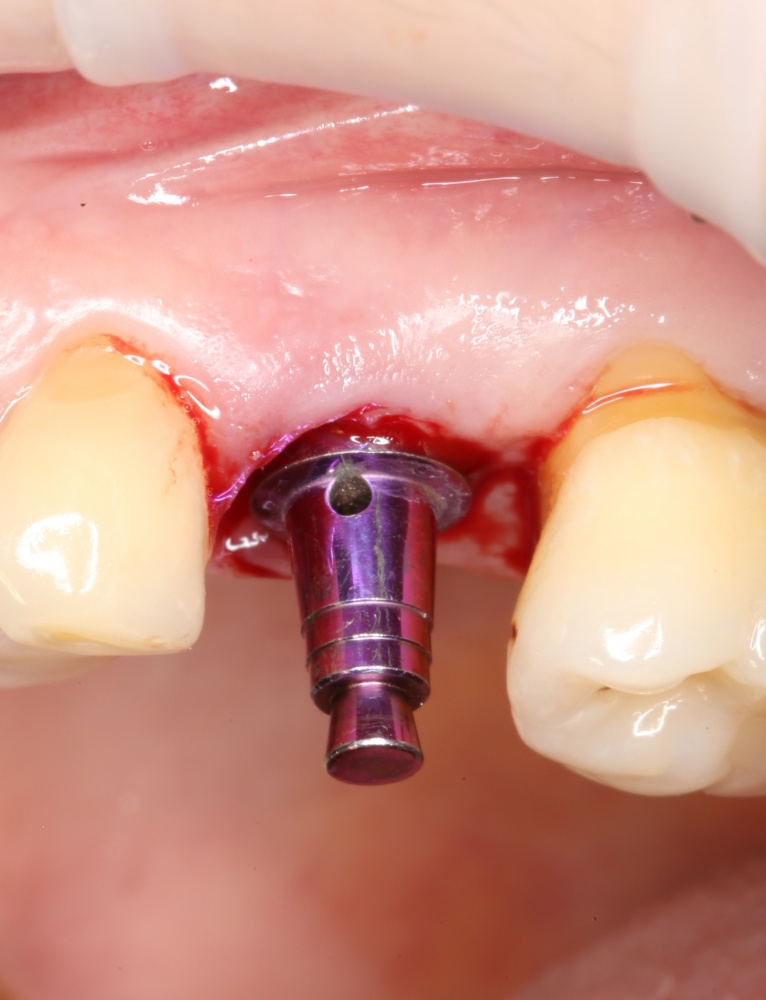

Рекомендации по установке имплантов. Для всех. Часть V.